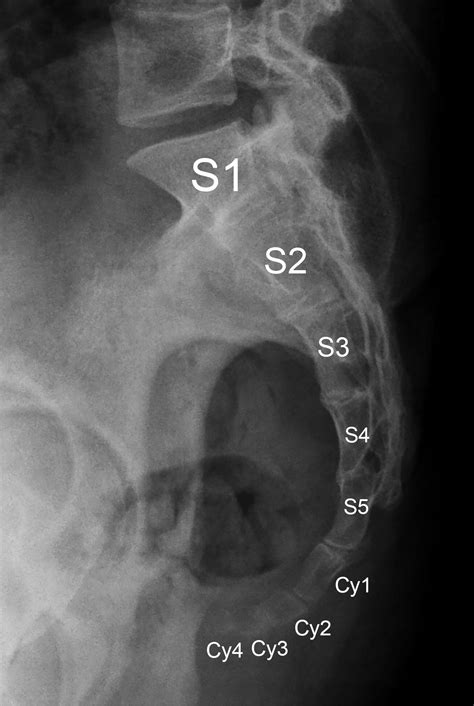

The sacrum and coccyx are essential components of the human spine. The sacrum is a triangular bone located at the base of the spine, formed by the fusion of five vertebrae. It connects the spine to the pelvis and plays a crucial role in supporting the body’s weight and facilitating movement. The coccyx, often referred to as the tailbone, is a small, triangular bone located at the bottom of the sacrum. It consists of three to five fused vertebrae and provides attachment points for various muscles and ligaments.

Interpreting Sacrum Coccyx X Ray results requires expertise in radiology. Healthcare professionals look for various signs and abnormalities in the images. Some common findings include:

• Fractures: Visible breaks or cracks in the sacrum or coccyx

• Dislocations: Misalignment of the sacrum or coccyx

• Degenerative changes: Wear and tear of the bones, often seen as bone spurs or narrowing of the joint spaces

• Tumors: Abnormal growths or masses in the bone

• Infections: Signs of bone infection, such as osteomyelitis

• sacrum coccyx x ray anatomy